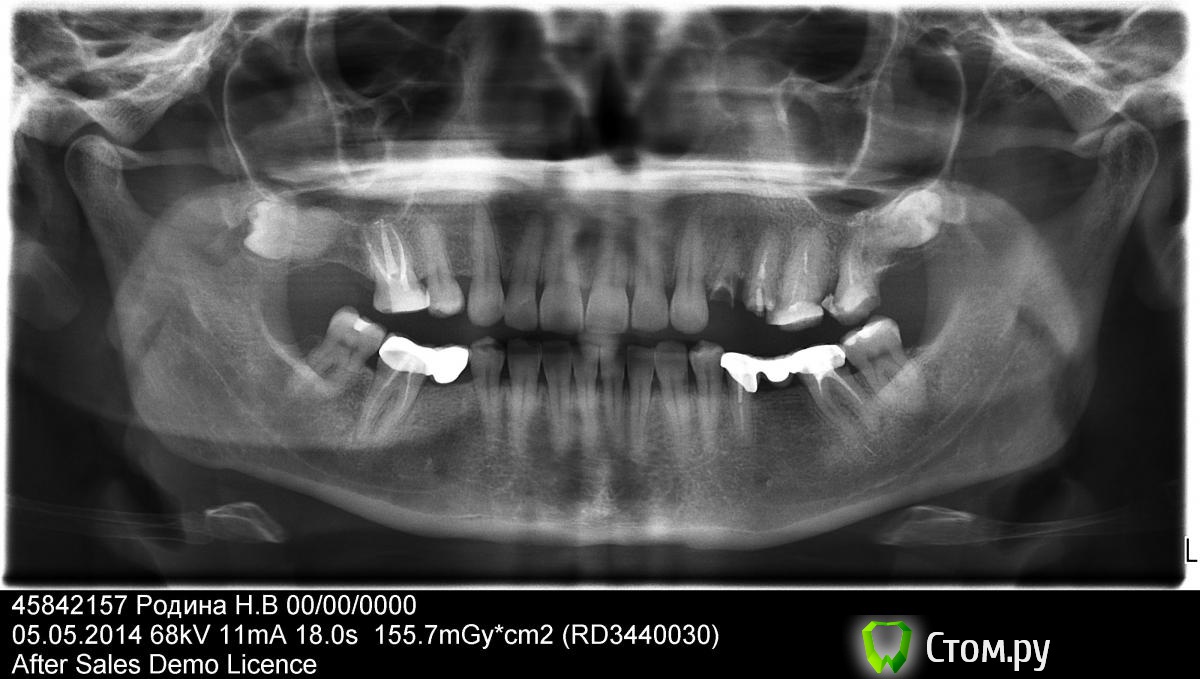

Барни Опубликовано 5 мая, 2014 Поделиться Опубликовано 5 мая, 2014 Здравствуйте! Помогите, пожалуйста, определиться с лечением.Зуб 6 в\ч справа пролечен полгода назад. Когда его лечили, то сказали сделать контрольный снимок через 6 мес и если на зубе останется киста, то зуб надо удалить.1. Осталась ли киста на зубе?2. Качественно ли запломбированы каналы (могу ошибаться, но на мой взгляд по середине запломбированного зуба какое-то затемнение – может плохо запломбировали)? В данный момент нахожусь перед выбором – доверить ли перелечивание остальных зубов с каналами тому доктору, который перелечивал зуб 6, или нет (тем более цена лечения данного зуба– сложная распломбировка четырех каналов и еще какой-то дополнительный канал?, лечение, запломбировка были в районе 18 т.р., за каждый зуб подлежащий лечению была озвучена такая же цена). Заранее спасибо за ответ. Ссылка на комментарий

Гарриевич Опубликовано 5 мая, 2014 Поделиться Опубликовано 5 мая, 2014 Нужен прицельный снимок этого зуба до лечения и прицельный снимок сегодняшний. По ОПТГ не четко виден дистальный канал зуба и мы не знаем как было до лечения 1 Ссылка на комментарий

Барни Опубликовано 5 мая, 2014 Автор Поделиться Опубликовано 5 мая, 2014 Нужен прицельный снимок этого зуба до лечения и прицельный снимок сегодняшний. По ОПТГ не четко виден дистальный канал зуба и мы не знаем как было до лечения Снимка зуба до лечения нет, только ОПТГ. А по-поводу кисты на этом зубе в данный момент- есть киста или нет? Ссылка на комментарий

Барни Опубликовано 5 мая, 2014 Автор Поделиться Опубликовано 5 мая, 2014 И еще беспокоит вопрос по-поводу затемнения по середине запломбированного зуба 6 в/ч справа - может ли это означать, что зуб запломбирован не совсем качественно (т.е. это некая пустОта, которая потом может привести к воспалению) Ссылка на комментарий

Stomart Опубликовано 5 мая, 2014 Поделиться Опубликовано 5 мая, 2014 И еще беспокоит вопрос по-поводу затемнения по середине запломбированного зуба 6 в/ч справа - может ли это означать, что зуб запломбирован не совсем качественно (т.е. это некая пустОта, которая потом может привести к воспалению)По середине пустоты точно нет, а вот на всё остальное можно ответить по прицельном снимку, как сказал коллега выше. Ссылка на комментарий